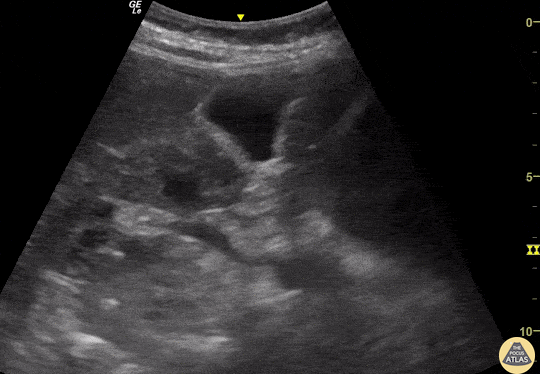

A 84-year-old female presented to the ED in decompensated heart failure. During the POCUS of her RUQ we incidentally identified this simple renal cyst; also note a single calculi within her gallbladder. Josiane Almeida, Emergency Physician Department of Marilia Clinic Hospital, Sao Paulo- Brazil